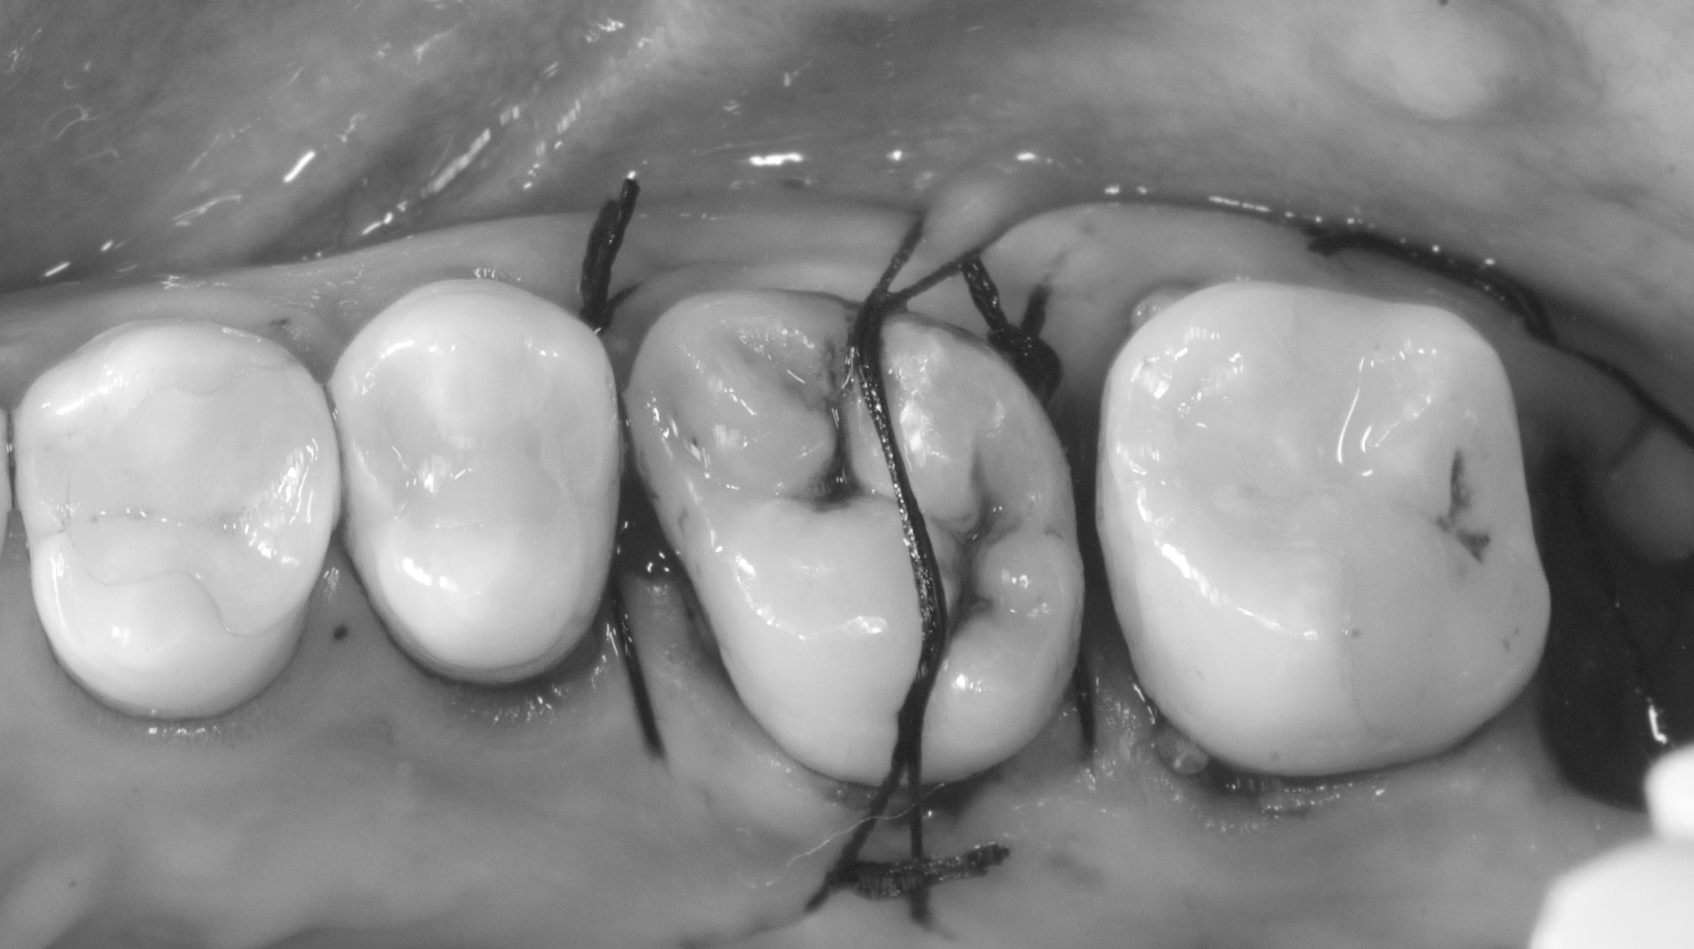

歯の移植って簡単にできるの???改変版

歯の移植って簡単にできるの???